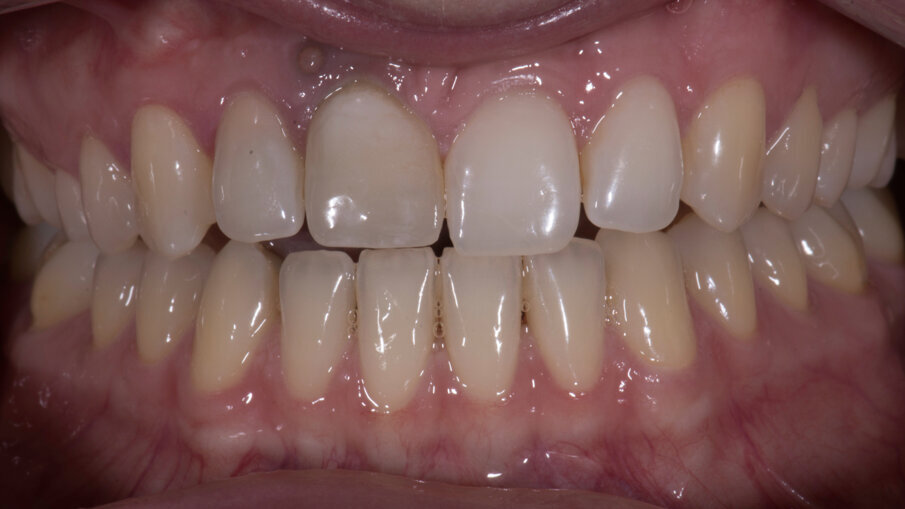

- Fresatura del dente protesico e sua finalizzazione

Il dente progettato è stato fresato utilizzando un cubetto di disilicato di litio forato e a bassa translucenza per meglio mascherare il grigiore del titanio del Tbase. Dopo avere scolpito la tessitura superficiale, il dente è stato lucidato utilizzando gomme con diverso grado di abrasività al fine di diversificare le diverse aree del dente rendendolo più naturale e in armonia con i denti vicini (Figg. 33-35). In corrispondenza della gengiva aderente è evidente un tatuaggio relativo alla posizione della pregressa fistola che potrà essere eliminato in qualsiasi momento qualora la paziente lo richiedesse. Le immagini ad 1 anno mostrano la stabilità nel tempo dell’ottimo risultato ottenuto (Figg. 36, 37).

Fig. 33_Prova delle forme e verifica del grado di compressione dei tessuti molli vestibolari.

Fig. 34_Dente protesico definitivo dopo le opportune fasi di finalizzazione.